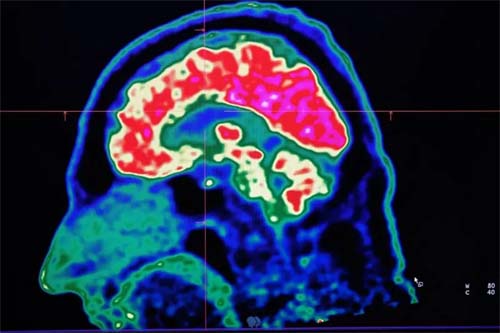

O cérebro, que gera calor próprio ao funcionar, depende de uma eficiente regulação térmica para manter suas funções. A exposição a altas temperaturas pode comprometer a transmissão de sinais entre neurônios e alterar processos cognitivos, afetando o humor, aumentando irritabilidade, agressividade e depressão.